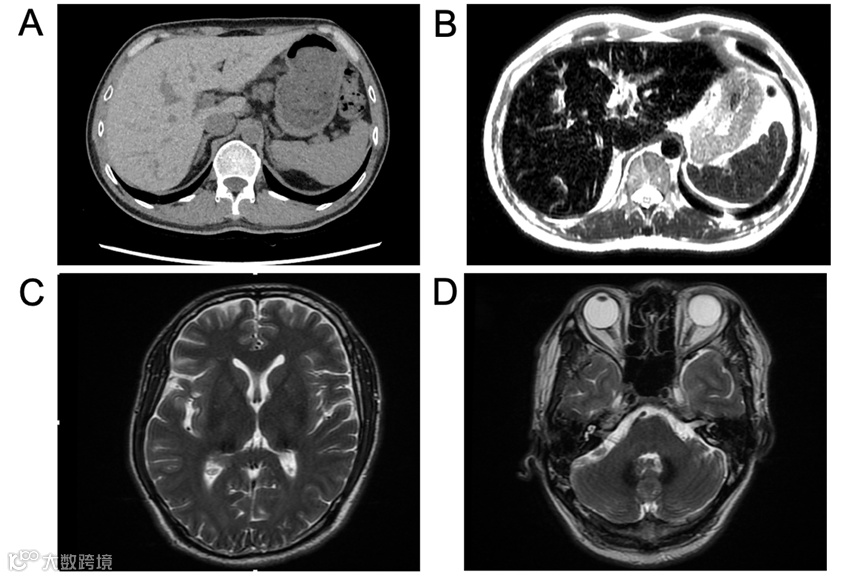

患者45岁男性,因“失眠20个月,腹胀不适2个月”入院。用药史及家族史无特殊。20个月前患者因“睡眠差、失眠”在当地医院诊断为“糖尿病”,发现血清铁蛋白2233 ng/mL,铜蓝蛋白< 0.024 g/L,肝脏CT值85.62 HU(图A)。2月前出现腹胀不适,查铁蛋白19710 ng/mL,ALT 301 U/L,AST 190 U/L,当地医院给予中药及护肝药物治疗,肝功能有所好转,病因未明,入我院行进一步诊治。

查体:胸前毛细血管扩张(+),无肝掌及蜘蛛痣。实验室检:血红蛋白118 g/L,白细胞和血小板计数正常,网织红细胞3.09%。肝功能及凝血功能基本正常,血糖 15.27 mmol/L,总胆固醇5.19 mmol/L,血清铁14.4 μmol/L,转铁蛋白饱和度45.1%,糖化血红蛋白6.2%。肝炎病毒标志物、自身免疫性抗体检查均为阴性。彩超肝胆脾胰未见明显异常。眼科:视网膜平伏,未见出血或渗出。腹部MRI-T2相显示肝脏、胰腺及脾脏明显低信号(图B)。头颅MRI显示双侧丘脑、基底节区和齿状核存在对称性斑片状短T2信号(图C、D)。骨髓穿刺涂片、组织病理学活检和染色体核型分析均未发现异常。肝脏穿刺活检显示慢性轻度炎症性肝损伤(G1S1)改变,肝细胞和库普弗细胞内有显著的含铁血黄素沉积,普鲁士蓝染色呈阳性(图E-H)。